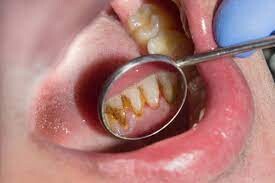

While your dentist and dental hygienist can typically detect supragingival calculus visually, dental professionals also receive extensive training using equipment other than their eyes. One such example, according to the IJDHS review, is an instrument known as a dental explorer, which helps the dental professional feel and remove calculus. A scaler is another common handheld instrument used to remove calculus above the gumline, as a review in the Saudi Dental Journal notes. In addition to these, new technologies — such as ultrasonic and laser tools — have also emerged to help dentists and hygienists detect and remove calculus.

It's important to remove calculus as soon as it's detected to prevent further bacteria buildup and retain gum health. The ADA notes that as supragingival calculus develops, the gums can become swollen and bleed easily. This condition, termed gingivitis, can worsen into a more serious form of gum disease if left untreated.